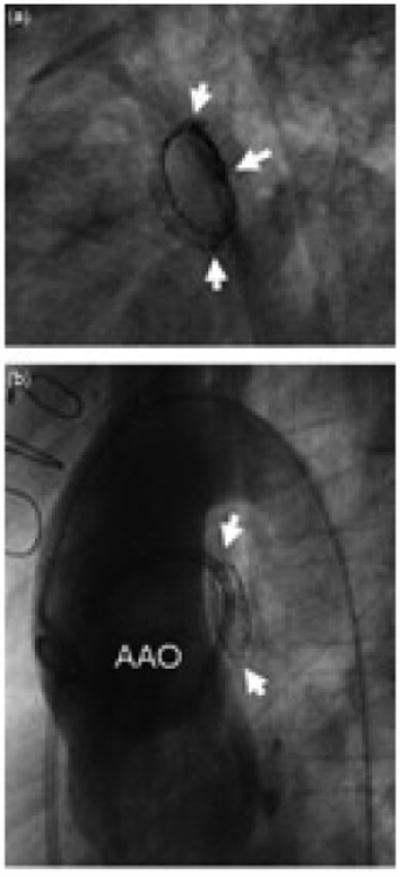

Figure 1.

Fractured central right pulmonary arterial stents in two patients: (a) one with tetralogy of Fallot and pulmonary atresia, and (b) one with common arterial trunk. Both stents were posterior to the ascending aorta, and were severely compressed in the anteroposterior dimension, assuming a lenticular configuration. The stent in (a) is fractured along three axial planes: superior, inferior, and posterior, as indicated by the arrows. The stent in (b) is fractured along the superior and inferior planes (arrows). The relationship between the stent and the large ascending aorta is demonstrated by the aortogram in (b).

Factors associated with increased risk of fracture by univariable analysis, compared with controls, are summarized in Table 2. By multivariable logistic regression, placement in close apposition to the ascending aorta (p = 0.001) and a larger expanded diameter of the stent (p = 0.002) were independent risk factors for fracture. In most cases of fracture, the stent was placed in the central right pulmonary artery, posterior to the ascending aorta (Fig. 1), but stents in the left pulmonary artery were also observed to fracture. Fracture of left pulmonary arterial stents was seen most often in patients with transposition repaired with an arterial switch operation, in whom translocation of the pulmonary arteries anterior to the ascending aorta may leave the branches draped across the ascending aorta anteriorly (Fig. 3), or in patients with a functionally univentricular circulation and a reconstructed aortic arch (Fig. 2). In 1 patient, with crossed pulmonary arteries after repair of common arterial trunk, the right pulmonary artery passed posterior and lateral to the ascending aorta and directly beneath the central part of the left pulmonary artery. The stent, which was compressed between these 2 vessels, fractured in multiple planes and a fragment embolized to the distal pulmonary artery.

In our experience, in situ fracture of stents used to treat central pulmonary arterial stenosis is relatively common. Although the design of our study does not allow a true estimate of the incidence of fracture, or of time to failure of the initial stent, we found that, of pulmonary arterial stents evaluated by catheterization at least 3 years after placement, one-fifth were fractured. Pulmonary arterial stents implanted in environments exposed to large cyclic external compressive forces appear to be particularly susceptible to fracture. Stents juxtaposed to the ascending aorta, most often in the central right pulmonary artery, posterior to the ascending aorta, had the highest risk of fracture. Larger stents, both in length and deployed diameter, were also more prone to fracture, which may speak to environmental effects resulting in an increased likelihood of compression, or to stent-related factors such as size- dependent differences in biomechanics. Patient-related factors associated with higher risk of fracture included a diagnosis of common arterial trunk or transposition after an arterial switch operation, and the presence of a right aortic arch. These factors are most likely important because of their association with increased risk of pulmonary arterial compression. For example, the space between the ascending and proximal descending aorta may be relatively small when the aortic arch is right-sided, or in patients with a particularly large aortic root or ascending aorta, as is often seen in association with common arterial trunk (Fig. 1), which may increase the likelihood of compression of the right pulmonary artery. Similarly, after the arterial switch operation with the Lecompte manoeuvre, the branches of the pulmonary trunk may be draped around, and consequently subject to compression by, the ascending aorta (Fig. 3). In fact, 4 of the 11 fractured stents in the central left pulmonary artery in this series were in patients who had undergone an arterial switch operation. Other circumstances in which stents in the left pulmonary artery fractured were in patients with tetralogy of Fallot, in whom the angle of origin of the left pulmonary artery from the pulmonary trunk is abnormally acute and prone to kinking, and in patients with functionally univentricular disease who had undergone reconstruction of the aortic pathway, and subsequently developed compression and stenosis of the central left pulmonary artery by the large neo-ascending aorta anteriorly (Fig. 2).

The manifestations of fracture may vary considerably. The effect of fracture and compression on luminal size and haemodynamic obstruction is a function both of the relief of stenosis from angioplasty and stenting in the first place, and the cross-sectional area of the lumen. When exposed to very high or complex multiaxial compressive forces, a fractured stent may collapse almost completely, or fracture along multiple planes, resulting in a vascular cross-section that takes a lenticular shape (Fig. 1). Severe eccentricity was observed in one-fifth of fractured stents, and in three-tenths of cases there was severe obstruction of the stented pulmonary arterial segment (Fig. 3). On the other hand, most of the fractures identified were associated with modest collapse and mild obstruction. In some of these cases, the compressive forces acting on the stent may be such that very little deformation of the cross-sectional geometry occurs once the point of plastic deformation has been reached, and in others, the fractured edges of the stent overlap, with the contour of the separate segments remaining more or less intact, resulting in a relatively circular cross-sectional area, only with a smaller diameter (Figs. 2 and 4).